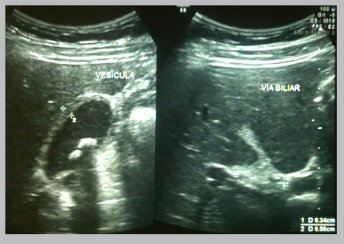

Paciente masculino de 30 años de edad con diagnóstico de colelitiasis desde hace dos años en los cuales ha presentado varios episodios de dolor en hemiabdomen superior derecho. Acudió a la sala de emergencia de Hospital Carlos Andrade Marín con dolor abdominal tipo cólico de doce horas de evolución, de intensidad 8/10, localizado en epigastrio e hipocondrio derecho, acompañado de vómito por varias ocasiones. Por el cuadro el paciente se había automedicado analgésicos sin que ceda el dolor. No refiere ictericia, acolia, ni coluria. Al examen físico sus signos vitales se encontraron estables. Los hallazgos positivos fueron: dolor a la palpación en hipocondrio derecho, Signo de Murphy (+) y resto de examen normal. Se realizaron exámenes complementarios que demostraron leucocitosis con neutrofilia, función renal y hepática normales; el ultrasonido abdominal reportó colelitiasis con cálculos de 11 y 12 mm de diámetro, paredes de vesícula engrosadas y vías biliares intra y extra hepáticas no dilatadas; foto 1.

Foto 1 Ultrasonido abdominal. se observa colelitiasis con cálculos de 11 y 12 mm de diámetro, paredes de vesí- cula engrosadas y vías biliares intra y extra hepáticas no dilatadas.